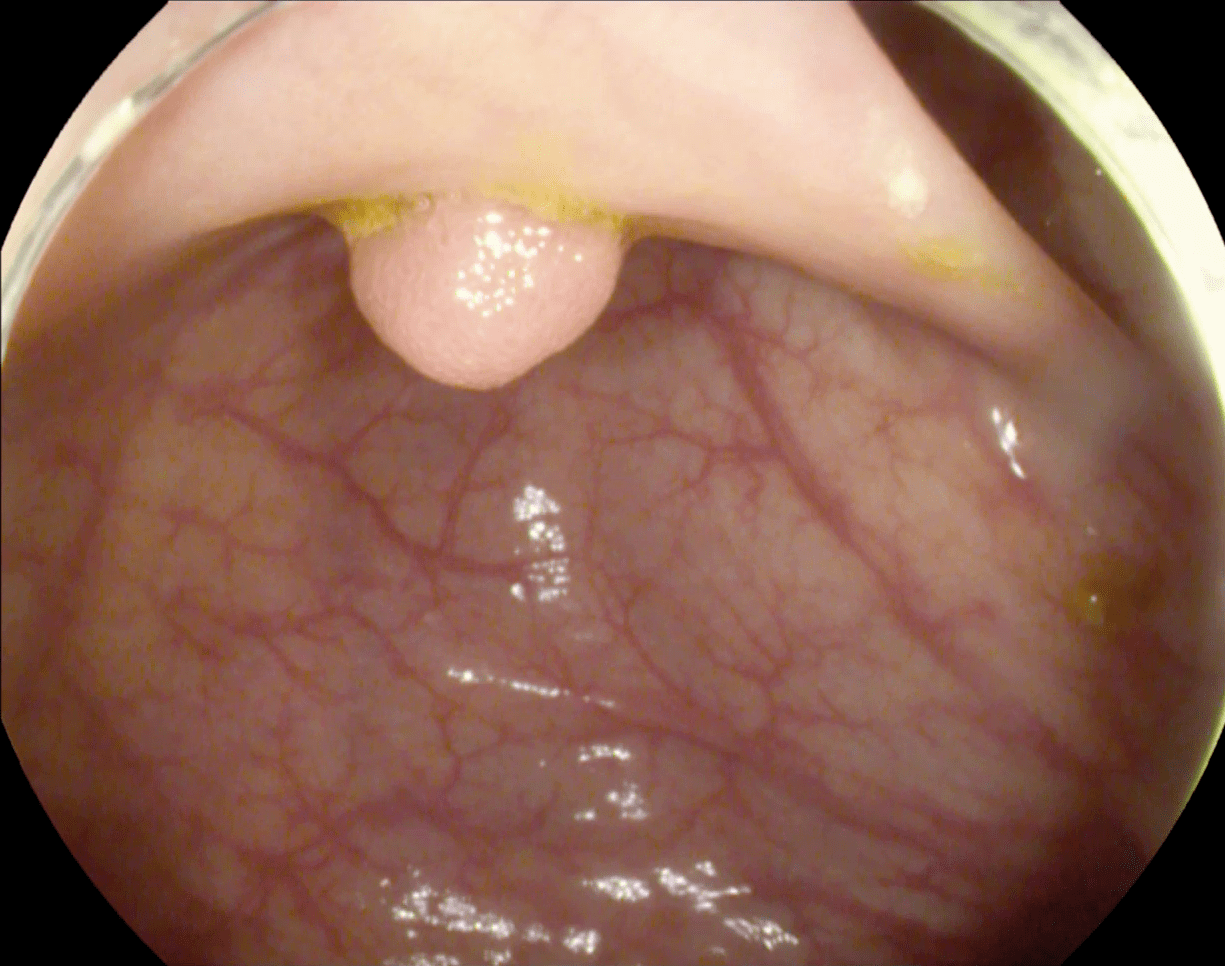

Diagnosing of distinct diseases within the small intestine is a time-consuming and hectic process for physicians. This has led to the introduction of technologies such as colonoscopy and wireless capsule endoscopy [1]. Colorectal cancer (CRC) is the second-highest cause of death by cancer worldwide with 880,792 deaths and a mortality rate of 47.60% in 2018 reported by American Cancer Society [2] 95% of CRC cases start with the appearance of a growth on the inner lining of the rectum or colon, called a polyp. Various types of polyps exist including, adenoma polyps, which can worsen into CRC. CRC is curable in 90% of cased assuming early detection [3]. Colonoscopy has emerged as minimally invasive and additional tool for investigating polyps by examining the gastrointestinal tract [3]. Colonoscopy relies on highly skillful endoscopists, and recent clinical investigations have shown colonoscopy misses 22%– 28% of polyps. This false negatives can lead to late diagnosis of colon cancer, resulting in a survival rate as low 10% [4].

The study used a publicly available dataset of polyp-frames obtained from the ETIS-Larib database [34], containing 196 polyp images. These images were obtained from 34 different colonoscopy videos of 44 different polyps with various appearances and sizes, having a resolution of pixels. The ground truth of polyp areas for polyp datasets is determined by expert video endoscopists. A CNN model trained with such a small amount of data is likely to be meaningless and unstable, so data augmentation was performed on the polyp dataset. Data augmentation had to be performed on the colonoscopy images by considering vivid variations. Otherwise over-fitting would have occurred. In a colonoscopy imagery, polyps exhibits large variations in location, color, and scale. Moreover, variations in brightness and definition also occur due varrying the view-point of the camera. Therefore, in addition to photometric distortions and geometric distortions, we also have considered zooming, shearing, and altering brightness as strategies for data augmentation.

The results shown in Fig. 6 are generated using the proposed deep CNN model on the augmented data set. It can be observed that the proposed model shows better polyp detection performance. As illustrated in Fig. 6, polyps within a frame can be identified at multiple positions, and as noted above in this case, the TP for detection is considered to be 1. The proposed deep CNN model performed better than other benchmark results in terms of the performance metrics listed above, as shown in Table. 2 and Fig. 6.

For single and deep layer of the proposed model, we have shown channel activation representing the convolutional kernels accurately detected the polyp. Fig. 7 shows different bright and dark parts corresponding to the spatial property of the object within the test images for single and deep layers. The top left is the test polyp image followed by top right detection output generated by proposed deep CNN model. The bottom left shows the single layer activation channel whole bottom right shows the deep layer for deeper feature analysis represented by green rectangular boxes. It can be observed in Fig. 7, that both single and deep layers are extracting polyp features with a high score, resulting in high polyp detection.